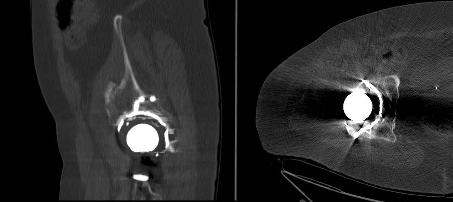

In order to clearly identify this defect and to plan the intraoperative procedure, an organized procedure as specified by ADC is the obvious approach. The diagnostic process is illustrated with an example in Figure 8. Figure 9 also shows the involvement of the posterior acetabular column in the CT imaging.

In summary, this shows a high-grade Type 3 C defect. According to the therapeutic ADC algorithm, this requires revision with metallic augmentation in the load-bearing zone of the superolateral and dorsal acetabular rim. Since this is a bony defect of >10 mm, an anatomical ileum tension band should be used for additional stabilization and preventing major relative movements. In our procedure, a modular support cup is used to meet the requirements with a caudal hook and the option of intraoperative adjustment with various augmentations and tension bands [10]. In addition, debrided bone defects should be augmented with biological material using impaction bone grafting outside of the loadbearing areas of the acetabular rim.